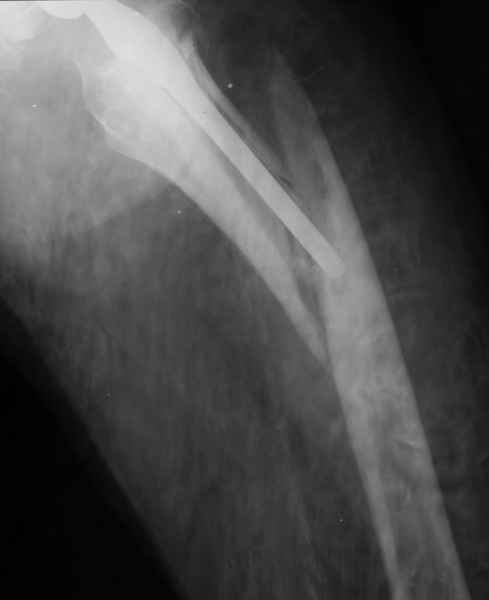

Уважаемые коллеги, продолжая дискуссию, начатую на "Вреденовских чтениях", хочу сказать, что принципиально сущестует два возможных варианта лечения.

1.Остеосинтез на ножке. Мне кажется, что применительно к этому случаю малоперспективный вариант. Синтез хорош, когда можно его выполнить в малоинвазивном исполнении и достигнуть стабильности. Действительно, если ножка б/цементной фиксации после этого не будет иметь фиксации, то ревизия не будет иметь проблем. В представленном случае стабильность синтеза сомнительная, а проведение доп.иммобилизации приведет к контрактуре суставов.

2. Применение ножки дистальной фиксации, мы отдаем предпочтение ножке Вагнера с фиксацией проксимального отдела на ножке. Более травматичное вмешательство, но при стабильной фиксации ножки реабилитация идет в обычном режиме.

Хочется показать два подобных случая, П-ка З. 72 лет и п-т Г. 80 лет. Сразу принимаю замечание, что это были ножки цементной фиксации, просто под руками не было бесцементника.